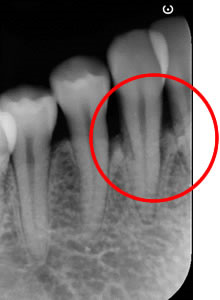

治療前のエックス線写真

歯を支えている骨が狭くて深い垂直性骨欠損です。

再生療法エムドゲインの適応症です。